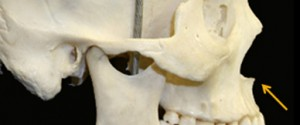

Anterior Nasal Spine | ANS

this is my x-ray, take away from here is that my ANS is projected AF.

is this usually good thing?